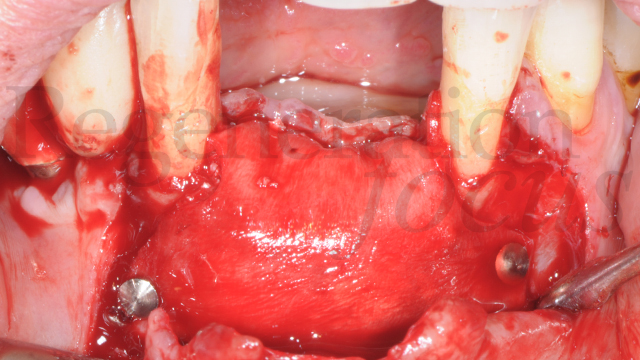

G.B.R. in area estetica con Circus Technique

Situazione ossea

Grave atrofia orizzontale e media atrofia verticale in 3.1-4.1

Paziente in buona salute generale, infermiera professionale, fumatrice.

Ha perso recentemente 3.1 e 4.1 per motivi parodontali e indossa una protesi mobile provvisoria, che non le consente una adeguata masticazione e fonazione.

Richiede, se possibile, riabilitazione mediante protesi fissa.